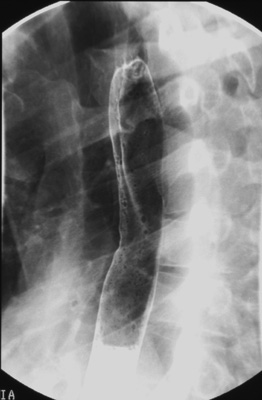

Ask the patient

to drink 1/2 cup of "bubbly barium" quickly and tell him not to belch. Scan

the length of esophagus while the patient swallows. Obtain two

double-contrast spot images - one of the upper and one of

the lower esophagus (including the gastric cardia) during maximal gas distention

after all gas bubbles have disappeared. Collimate the fluoroscopic image side-to-side before taking the esophageal spot images.